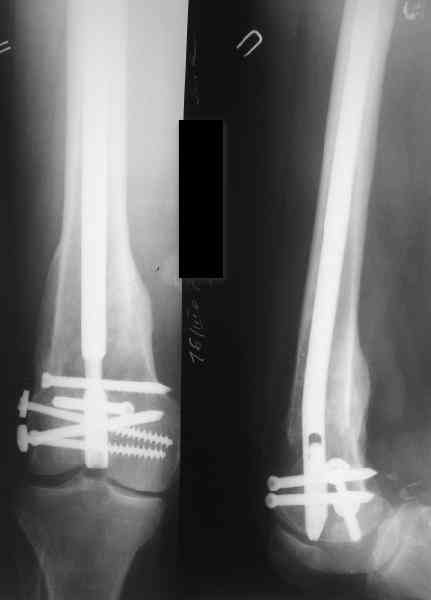

В приложении пример, как их использовали после остеотомии бедра по поводу сросшегося с вальгусом перелома, чтобы не дать гвоздю уйти во внутренний мыщелок.

Да, действительно красивый клинический пример: виден вальгус до операции и последующая коррекция углового смещения на "полярах". Я так понимаю, что в вашей клинике есть возможность использовать различные фиксаторы. Почему не использовали DFN? Спицы какие используете? Киршнера или Илизаровские? С виду очень тонкие...